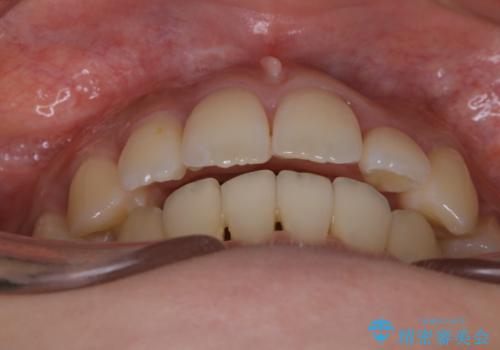

がたつきが強いガチャ歯。埋伏歯抜歯+矯正。すごいところに犬歯が埋まっていたのを抜いてワイヤー矯正治療

開窓して器具で力をかけても動く様子がなかったため抜歯とし、小臼歯を犬歯に見立てて治療を完了しました。

結果的に見た目の違和感もなく、期間の短縮にもつながりました。